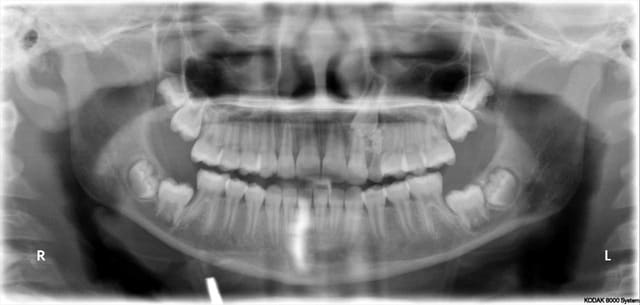

C’est étonnant ce que tu dis, j’ai moi-même toujours utilisé des ligatures métalliques pour tracter les dents incluses et pourtant je n’ai jamais observé de cicatrisations fibreuses ni de labourages de gencive. Je suis orthodontiste qualifié et je m'impose de les dégager moi-même chirurgicalement où qu'elles soient avant de les coller et ce depuis plus de trente ans !

Il m’arrive de temps en temps (très rarement) de coller directement la ligature sur la couronne d’une dent incluse, c’est alors l’extrémité en anneau de son toron que je colle. On a alors les mêmes avantages que tu décris mais on a aussi un inconvénient qui est le manque de liberté qu’on impose à la dent qu’on tracte, et dans les cas où elle est particulièrement loin et où sa venue est acrobatique, cette rigidité peut être un frein à son déplacement.

Comme tu le dis bien, la méthode avec chaînette telle que tu l’exposes n’est utilisable que lorsque la canine est très proche. Lorsque qu’elle est loin et que le placement d’une vis dans le septum n’est pas possible, que fais-tu ?

Dans ces deux cas-ci dont je joins les photos, je ne vois pas très bien comment tu aurais pu faire avec ta méthode. Le premier avait 4 canines incluses, j’ai utilisé un système traditionnel en haut (boutons collés sur les couronnes, ligatures et traction par cantilever) et des ligatures collées directement sur les couronnes et traction par CT8-1 en bas. Pour le second, je me suis servi de l’alvéole déshabitée de la 53 pour passer la ligature, avec un CT8-1. Dans ce dernier cas, où aurais-tu mis ta vis ?

Daniel